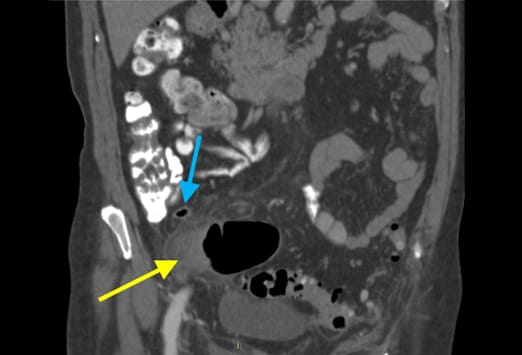

Die Abbildung auf der linken Seite zeigt eine einfache Appendizitis. Hier ist eine Verbreiterung und ein Ödem der Appendix zu sehen, mit einer erhöhten Kontrastmittelaufnahme der Appendixwand (blauer Pfeil) und einer geringen umgebenden Entzündungsreaktion. Beim Fortschreiten einer Appendizitis kommt es von der einfachen Form und einer nachfolgenden gangränösen Veränderung schließlich zur Perforation. Nach der initialen Obstruktion des Lumens kann es zu einer verminderten Perfusion kommen. Das Bild auf der rechten Seite zeigt eine gangränöse Appendizitis, bei welcher es zu einer Zunahme und einer Infiltration in das Mesenterium gekommen ist. Ein Appendikolith (gelber Pfeil) kommt ebenfalls zur Darstellung.